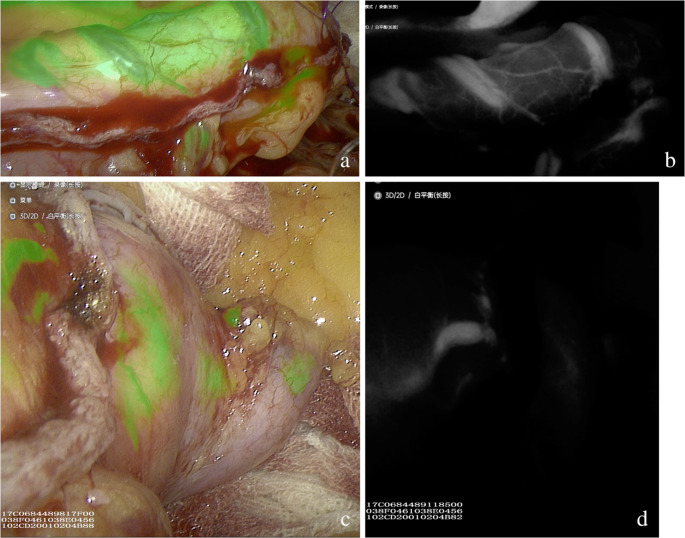

背景:近年来,随着研究人员发现吲哚菁绿(ICG)近红外荧光成像具有优异的组织穿透性,ICG荧光血管造影(ICG- fa)在各种腹腔镜手术中的应用日益广泛,并取得了显著的治疗效果。然而,其在腹腔镜袖式胃切除术(LSG)中的应用尚未被广泛报道。材料与方法:回顾性分析2021年9月至2024年11月在我院临床医学中心行LSG的291例患者的临床资料。将患者分为两组:A组195例(术中未使用ICG-FA), B组96例(术中使用ICG-FA)。采用统计软件对数据进行处理和分析。结果:A组沿钉线的平均失血量为6.53±1.69 mL, B组为2.57±1.81 mL (p结论:我们机构数据的发现表明,尽管ICG-FA在统计上显著减少了钉线出血(由于缝合针穿刺),缩短了平均手术时间,缩短了平均住院时间,但与其他腹腔镜手术相比,其在LSG治疗病状肥胖的临床益处似乎有限。此外,ICG-FA并没有减少术后并发症的发生率,如胃漏或出血。

Background: In recent years, as researchers have discovered that indocyanine green (ICG) near-infrared fluorescence imaging offers excellent tissue penetration, the application of ICG fluorescence angiography (ICG-FA) in various laparoscopic procedures has become increasingly widespread and gets significant therapeutic efficacy. However, its use in laparoscopic sleeve gastrectomy (LSG) has not been extensively reported.